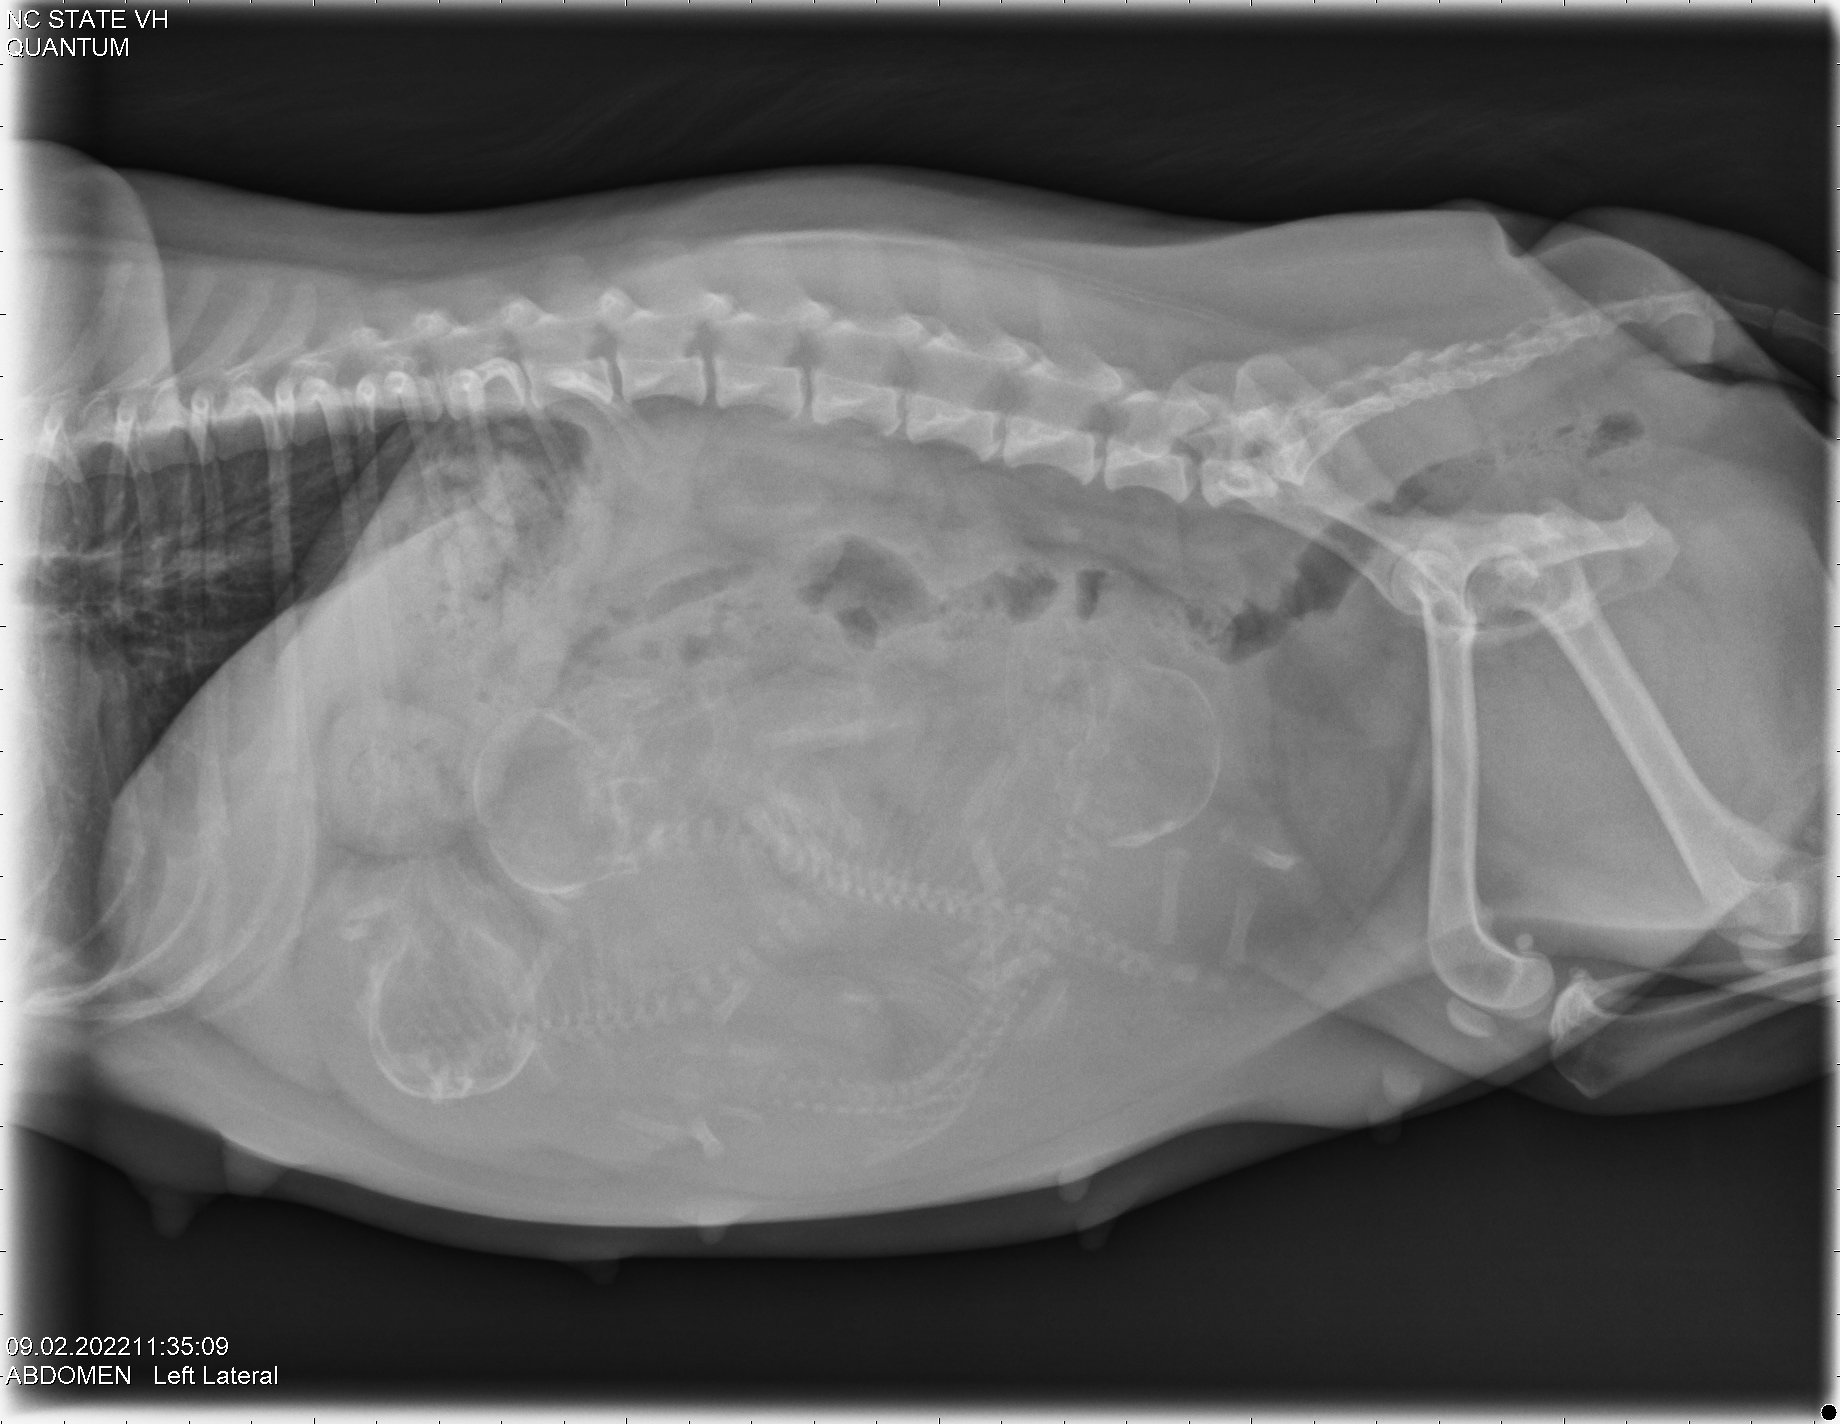

Today was x-ray day! Because ultrasound is so unreliable in counting the number of puppies, late in a canine pregnancy my repro vets at NC State University take an x-ray to get an accurate count of the number of puppies. Boo is carrying three puppies! (The mean average size of a Norwich litter is 2.7.)

Here are the x-ray pictures:

Using the x-ray, by comparing the size of the puppy skulls and the size of Boo's pelvic opening, the vets are also able to give a recommendation as to whether Boo needs a cesarean section (c-section) or if I should let her try to give birth to the puppies. Unfortunately the puppy skulls are almost the same size as Boo's pelvic opening, so the recommendation is that Boo should have a c-section. So this is what we will do.